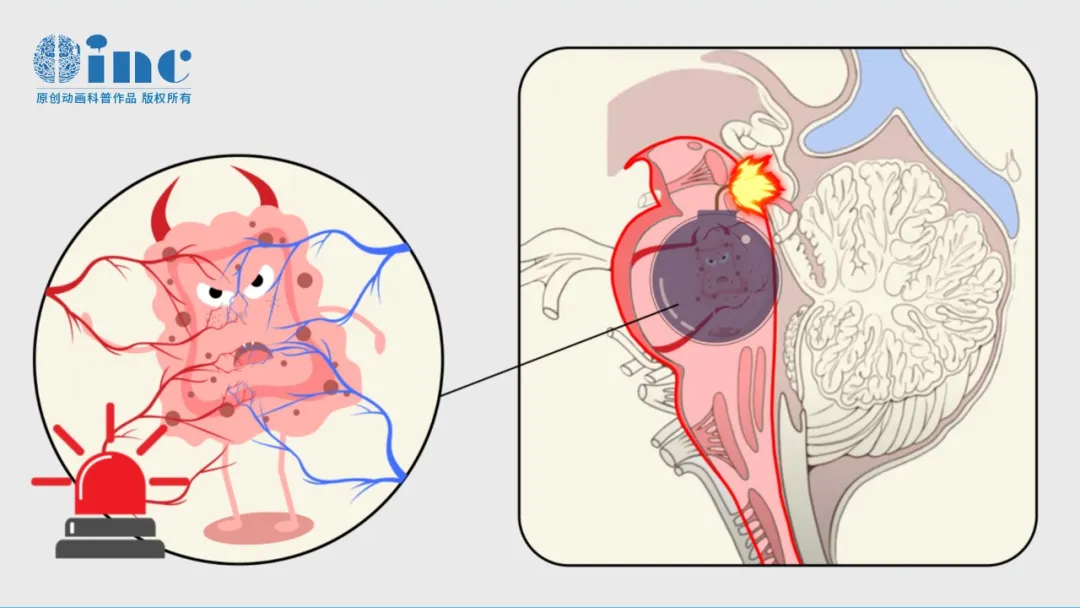

或许很多人存在疑惑,为何医生反复强调小宇病情凶险?这需要从桥脑的解剖位置与生理功能说起——桥脑作为脑干的重要组成部分,位于大脑与脊髓之间,相当于人体神经信号的“交通枢纽”,更是维持生命活动的“核心中枢”。

桥脑不仅承担大脑下行神经纤维的传导功能,控制躯体运动,同时也是躯体感觉上行传导通路的关键部分,使我们能够感知触觉、痛觉等;此外,它还负责调控呼吸、心跳、吞咽等基本生命活动,堪称维持人体正常运转的“总开关”。

鉴于桥脑功能至关重要,且该区域神经结构密集、空间极为有限,一旦发生病变(例如小宇所患的海绵状血管瘤),轻微操作失误即可导致不可逆的神经功能损伤: